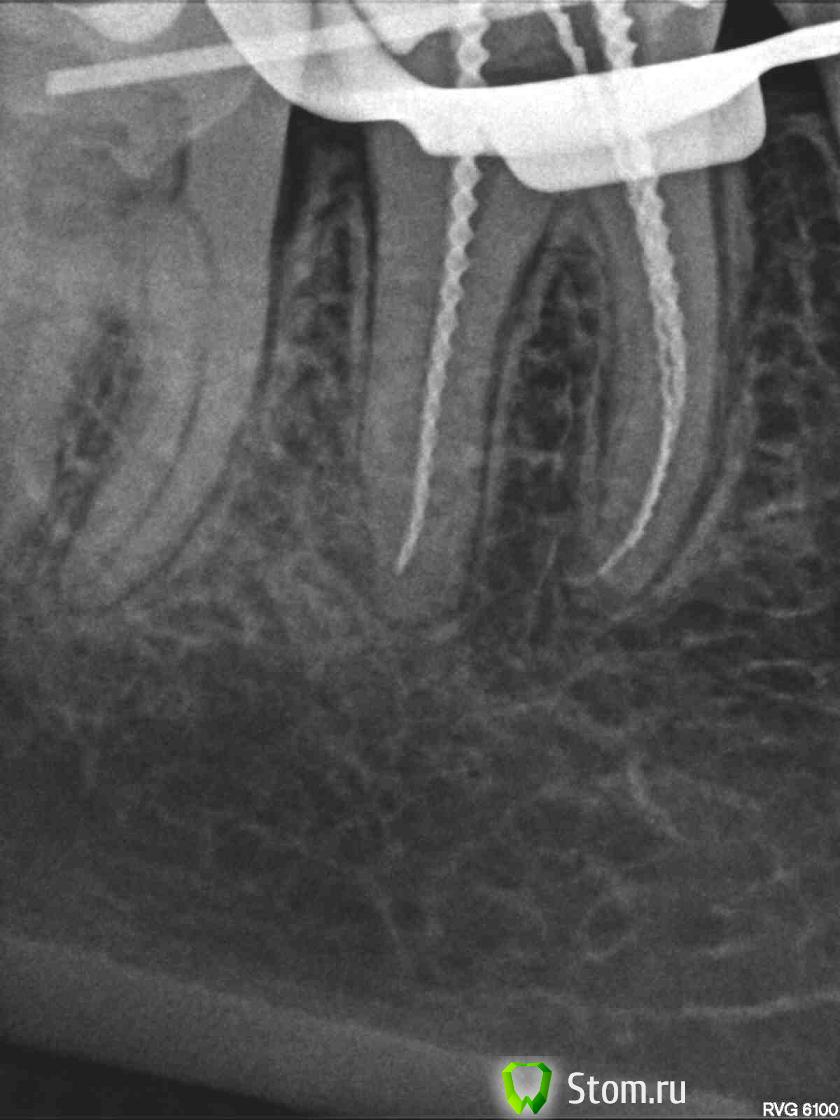

Anna_M Опубликовано 31 января, 2012 Автор Поделиться Опубликовано 31 января, 2012 (изменено) Сегодня все-таки депульпировали Закрыли метапастой под временную пломбу на 10 дней. В пульповой камере дентикль, каналы склерозированные. Проводниковая анестезия не подействовала, т.к. док не попал в нужный нерв по причине моей аномальной анатомии ветви нижней челюсти. Сделали инфильтрационную, но когда стали вскрывать пломбу, стало ясно, что тоже не действует. Кололи внутрипульпарно. Три раза. Так до конца и не обезболили, местами чуть из кресла не выпрыгивала. Когда включили аплок, было особенно больно. Док объяснил тем, что на дне канала остались кусочки пульпы, которым, ессно, было больно от проходящего через них тока. Контрольный снимок с файлами не делали, м.б., в следующее посещение сделают? Коффер надели с трудом, оторвали два брекета, но все равно из-под коффера подтекало в полость рта, я помигала доку, мол, "течет". Он залил щели ликвидамом. Доктор работал с микроскопом, нашел и обработал три канала. Оставшиеся кусочки пульпы, которые не удалось вытащить из-за того, что каналы слишком узкие, будем растворять получасовой экспозицией хлорки во время второго посещения. 1.Скажите, пожалуйста, может ли после депульпирования зуба и закрытия каналов гидроокисью сохраняться реакция на холод с той же интенсивностью и продолжительностью, как и до лечения?2.Стоит ли мне до следующего приема сделать снимок зуба на текущий момент (с гидроокисью в каналах)?3.Растворится ли оставшаяся органика в каналах за полчаса? Изменено 31 января, 2012 пользователем Anna_M Ссылка на комментарий

Anna_M Опубликовано 11 февраля, 2012 Автор Поделиться Опубликовано 11 февраля, 2012 И снова здравствуйте, уважаемые специалисты. Сегодня запломбировали термафилом... Ссылка на комментарий

ger_berra Опубликовано 11 февраля, 2012 Поделиться Опубликовано 11 февраля, 2012 Как ощущения?По снимкам гуд! Ссылка на комментарий

Anna_M Опубликовано 11 февраля, 2012 Автор Поделиться Опубликовано 11 февраля, 2012 Как ощущения? Спасибо, все хорошо! По снимкам гуд! Екатерина, Вы меня очень сильно обрадовали тем, что на снимках Вам все нравится! Спасибо! Ссылка на комментарий